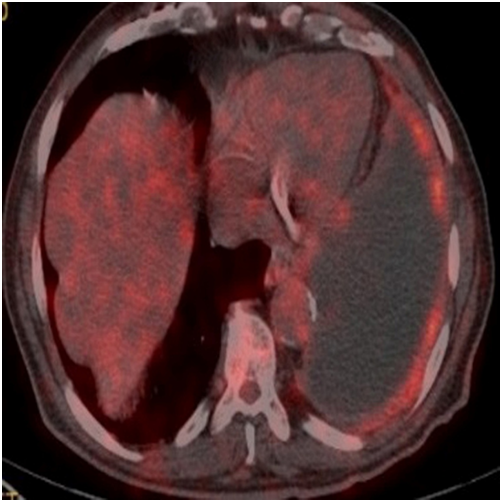

A sixty-year-old male patient has been placed a drain by thoracic surgeon upon seen massive fluid on the right in the chest x-ray due to shortness of breath. Partial decortication and pleurodesis were performed with VATS on the suspicion of malignancy in fluid cytology. Visceral and mucinous adenocarcinoma infiltration common in the parietal pleura was detected as a result of the biopsy. It was found as WT-1, Calretinin, Thrombomodulin, CK20, CK5/6, D2-40 were negative, TTF-1 was strong, CK7 was strong, CEA was weakly positive (Figure 3A) & (Figure 3B) in immunohistochemical staining. It was referred to our clinicfor treatment arrangements. There were fifteen p-year cigarette stories, he did not drink for 30years, he did not define asbestos exposure. FDG uptake (SUV max, 6-7.6) in the common pleural thickening areas which were evident in the upper and middle zone of the right hemithorax, FDG uptake in the right upper and lower paratracheal conglomerate lymphadenopathies (SUVmax, 7), subcarinal (SUVmax, 6) and left hilar lymph nodes (SUVmax, 3.8) was detected on PET-CT taken (Figure 4). The patient who was scheduled for chemotherapy did not accept the treatment and came out of follow-up.

Figure 4 FDG (SUV max 6-7.6) uptakes in diffuse pleural thickening areas evident in the right hemithorax upper and middle zone.